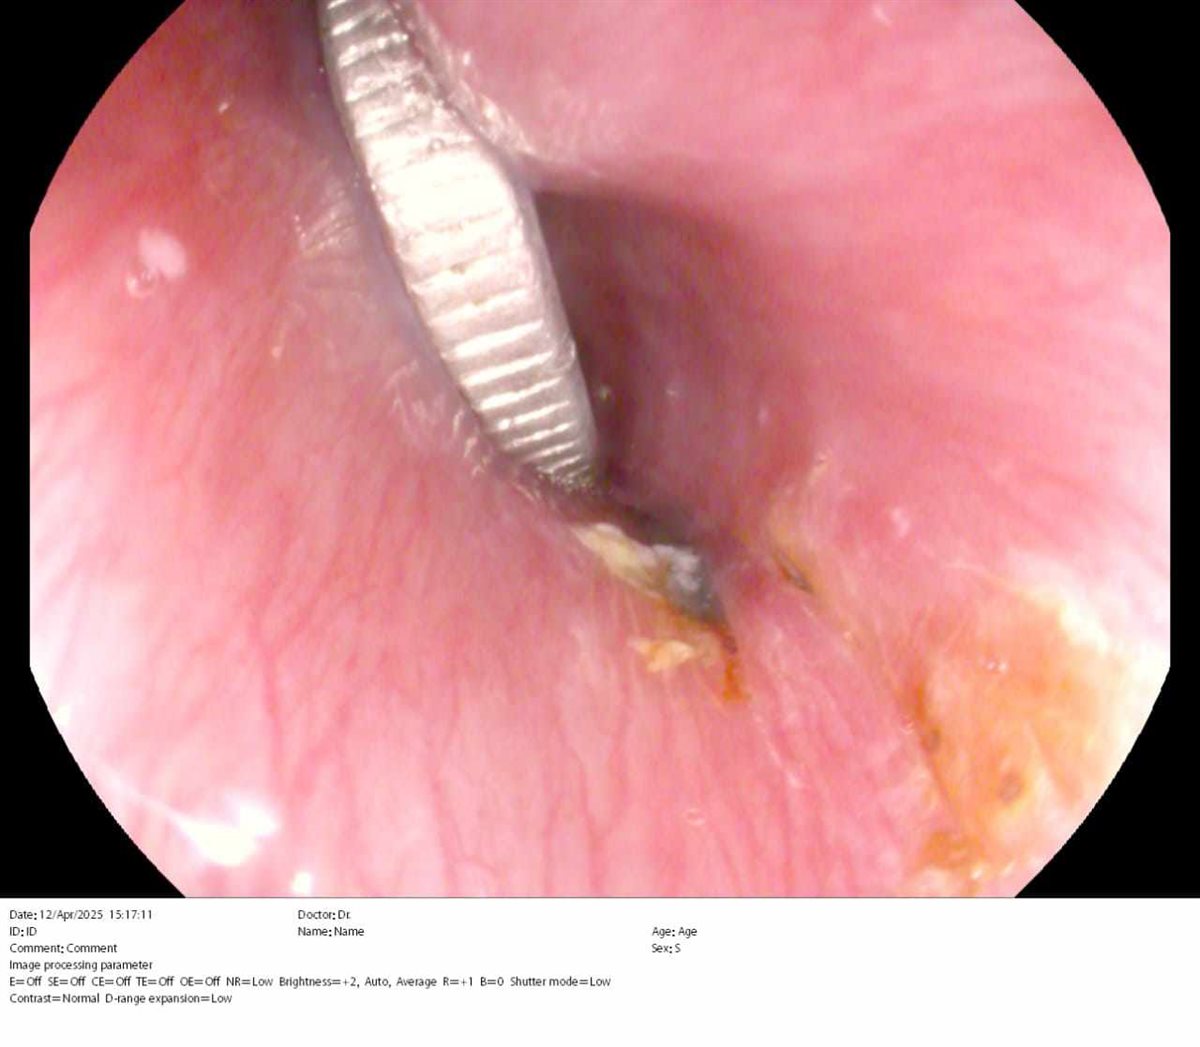

التعامل مع الحالة الأولى بإجراء منظارمعدة طوارئ للطفل واستخراج عملة معدنية علقت أسفل صمام المرئ العلوي

وأوضح الدكتورهاني مصطفى جميعة وكيل وزارة الصحة بالشرقية بأنه تم التعامل مع الحالة الأولى بإجراء منظارمعدة طوارئ للطفل واستخراج عملة معدنية علقت أسفل صمام المرئ العلوي، حيث ابتلعها منذ ثماني عشرة ساعة وأدت إلى انسداد في مجرى الطعام والتهابات بجدار المرئ بسبب ضغط العملة على جدار المرئ، وإنقاذ الطفل قبل حدوث ثقب في جدار المرئ.